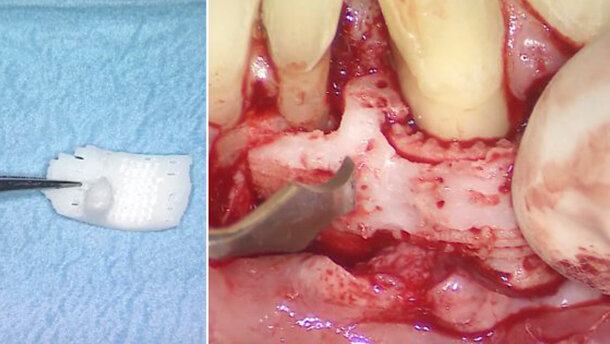

Secondo il rapporto, è stato utilizzato per il file dati in ingresso il formato STL (STereoLithography) per la produzione dello scaffold più adatto, partendo dalla TAC del difetto. La struttura è stata stampata utilizzando una sinterizzazione laser selettiva con policaprolattone in polvere contenente 4% di idrossiapatite.

I ricercatori hanno raccontato che il sito trattato è rimasto intatto per 12 mesi, a dimostrazione di un guadagno di 3 mm di attacco clinico e della copertura parziale della radice, senza segni di infiammazione cronica o deiscenza. Tuttavia, 13 mesi dopo la terapia, la struttura si è esposta.